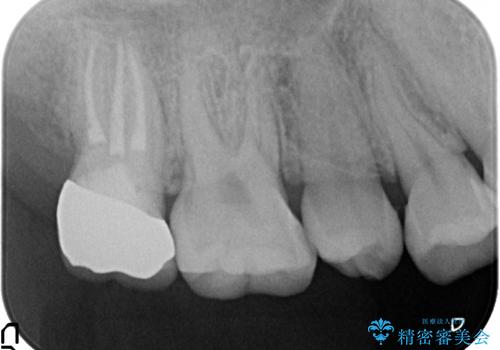

- 冷たいものを飲むと右上の奥歯がしみるので診て欲しいといらっしゃった方の症例です。

右上6番目、7番目の歯の樹脂が劣化していたため、虫歯除去後セラミックインレーによる修復を行いました。

当院のセラミックインレーはemaxという強度と審美性に優れた材料を使用しています。

またプレス方式でインレーを製作しているため、削り出しで製作するCADCAMより優れた適合性も持ち合わせており、虫歯が再発しにくい修復物です。